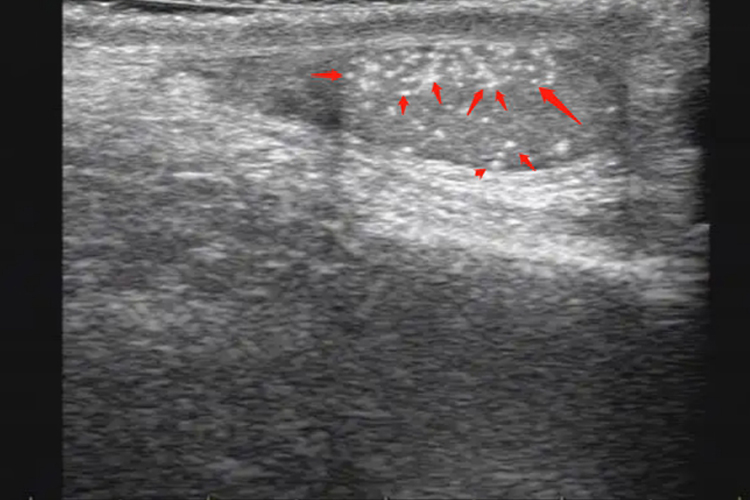

患者出现睾丸结石时,可用手指在睾丸外周触摸到一个或多个质地坚硬、表面光滑的结石感,或有结石摩擦感,合并炎症者有触痛,坠胀感明显。结石停留于射精管中阻碍精液排出时,可引起绞痛,阴茎勃起时或射精时,症状加重。患者进行超声检查时,可见双侧或单侧睾丸实质内弥散分布大量的点状强回声,后方无声影。